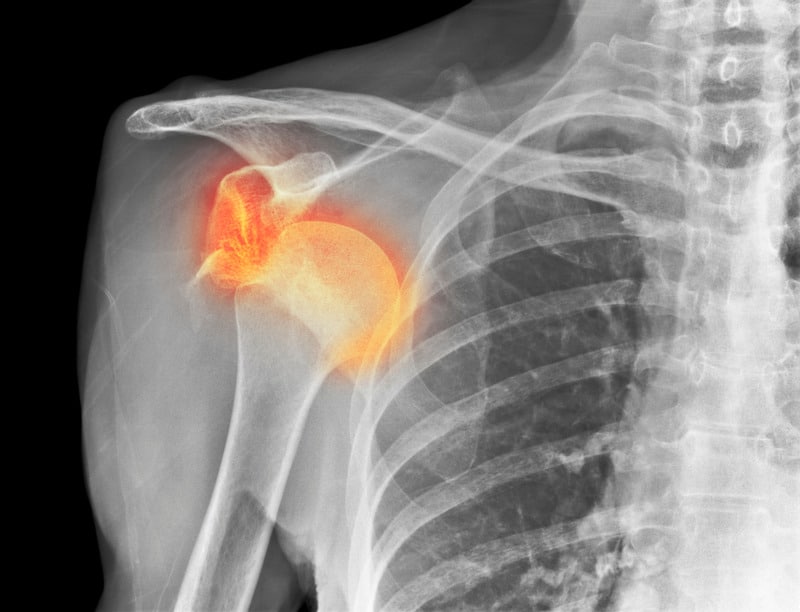

Xray of Shoulder Dislocation

A shoulder dislocation occurs when the head of the humerus is forcibly displaced from the glenoid cavity of the scapula(shoulder blade). This injury is most commonly anterior in nature and often results from high-impact falls where the arm is extended outward. Skiers frequently sustain this injury during sudden crashes or when attempting to break a fall with an outstretched arm.

The signs and symptoms of a shoulder dislocation include intense pain, visible deformity, swelling, and the inability to move the arm. Immediate management involves reduction of the dislocation by a trained professional, followed by immobilisation of the joint with a sling to allow for healing. Rehabilitation typically includes physiotherapy to restore strength and range of motion. If the shoulder continues to be unstable or further dislocates, then arthroscopic stabilisation may well be required.